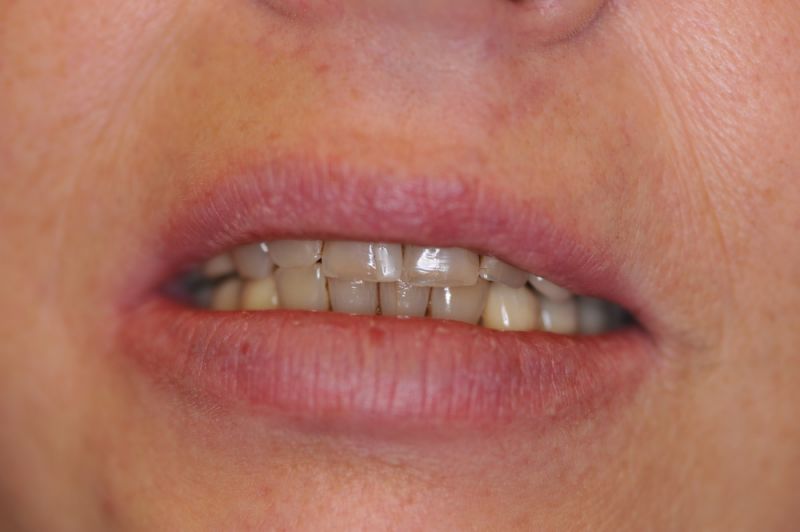

Schwierigster Fall aller Zeiten, praktisch beschwerdefrei. Patientin glücklich!

Der Fall einer Patientin aus Hamburg ist zwar bei weitem nicht der umfangreichste, oder gar teuerste Fall aller Zeiten, aber der Fall, der bei dem überschaubaren Umfang, das meiste Kopfzerbrechen bereitet hat und man darf es sagen, am Ende primär als sportliche Herausforderung gesehen wurde, ob man das überhaupt noch hinbekommt.

Und wir haben es hinbekommen! Die Patientin hat heute zum Ausdruck gebracht, dass sie das selbst nicht für möglich gehalten hätte.

Es war eine Kombination aus Schmerzen bis an die Suizidgrenze, beschränkten wirtschaftlichen Möglichkeiten, sehr stark eingeschränkten Möglichkeiten der für Implantate zur Verfügung stehenden Knochenverhältnisse in einem stark atrophierten Unterkieferseitenzahnbereich und zudem dann auch noch durch auftretenden Problemen bei der Implantatinsertion und nachfolgenden Versorgung der Implantate.